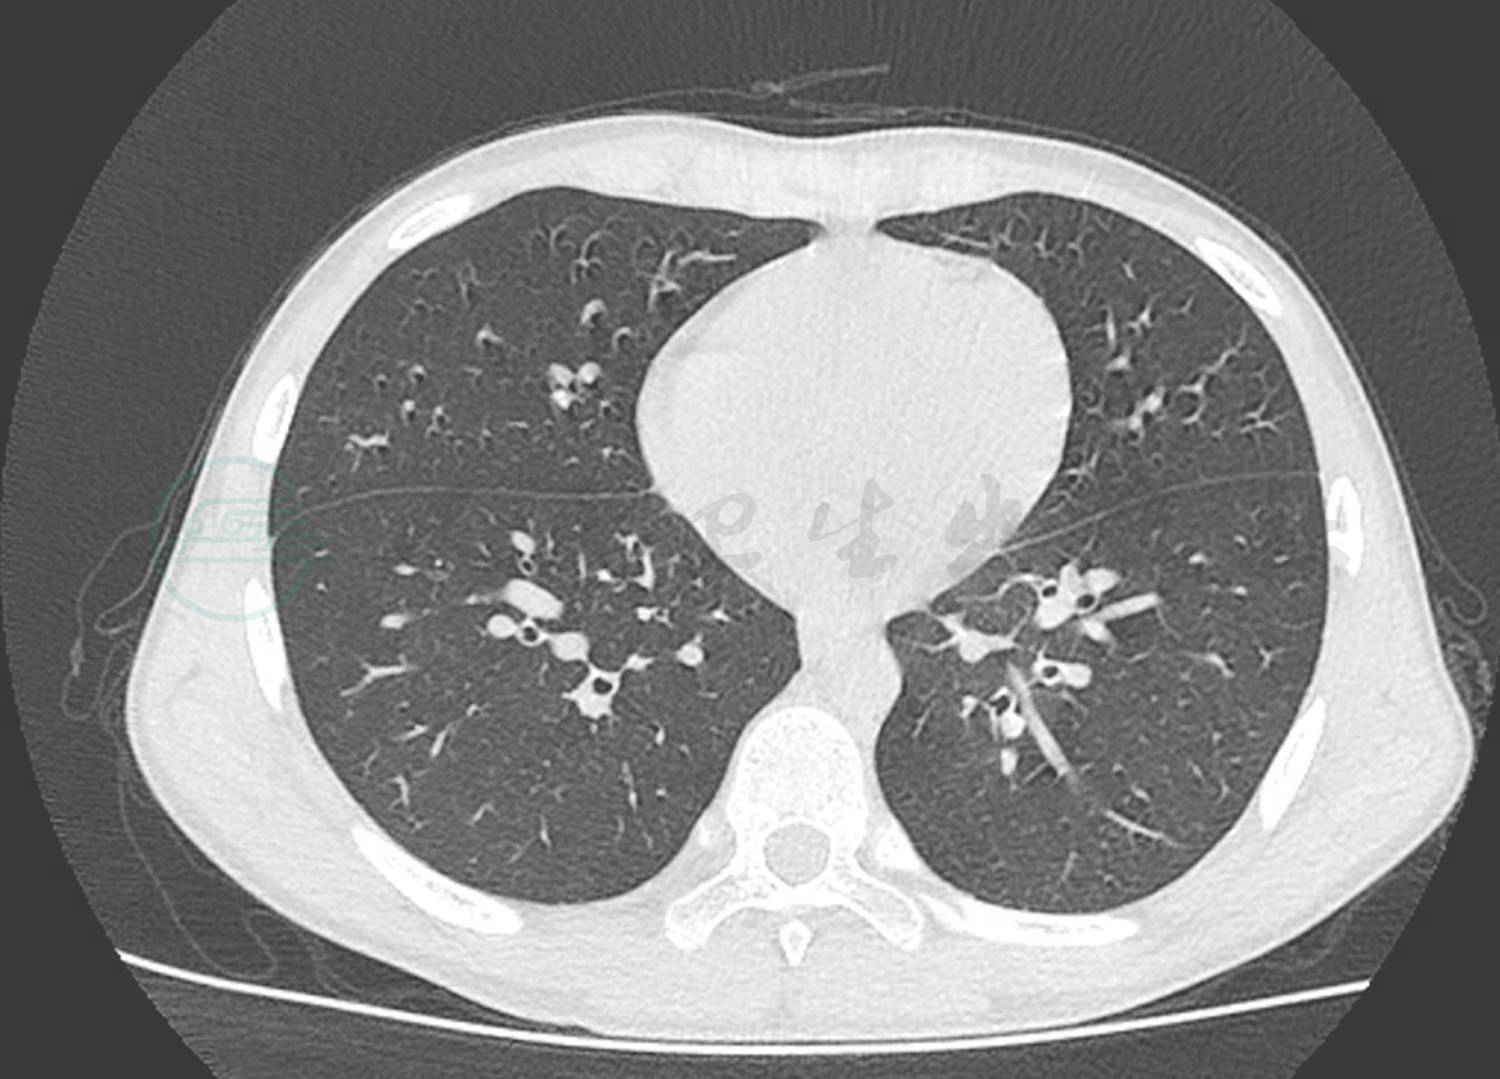

辅助检查:血常规:白细胞计数10.3×109/L,中性粒细胞百分比84.2%,淋巴细胞百分比8.3%,红细胞计数4.36×1012/L,血红蛋白126g/L,血小板 150×1012/L;CRP 87.2mg/L;降钙素原7.22ng/ml;DIC基本正常;肝功能正常;痰培养未见细菌真菌生长;血培养未见细菌生长;6天前肺CT显示双肺多发渗出,以右肺下叶为主伴有实变,双侧胸腔积液(图1);入院前1天肺CT显示双肺下叶实变范围较前增大。双侧胸腔、右侧叶间积液较前减少(图2)。

图1 入院前6天肺CT